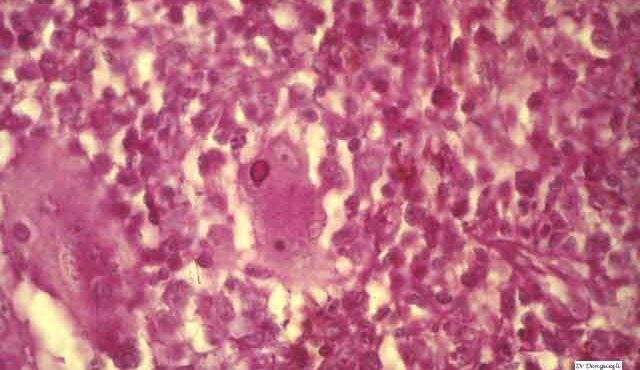

Read MoreBowen’s disease = داء بوفن OLYMPUS DIGITAL CAMERA OLYMPUS DIGITAL CAMERA OLYMPUS DIGITAL CAMERA Bowen disease Bowen disease is a full-thickness anaplasia of the epidermis, with loss of the normal maturation of its components. Keratinocytes are atypical and disorderly, often described as having a windblown appearance. Although the basal cell layer is intact, extension of […]